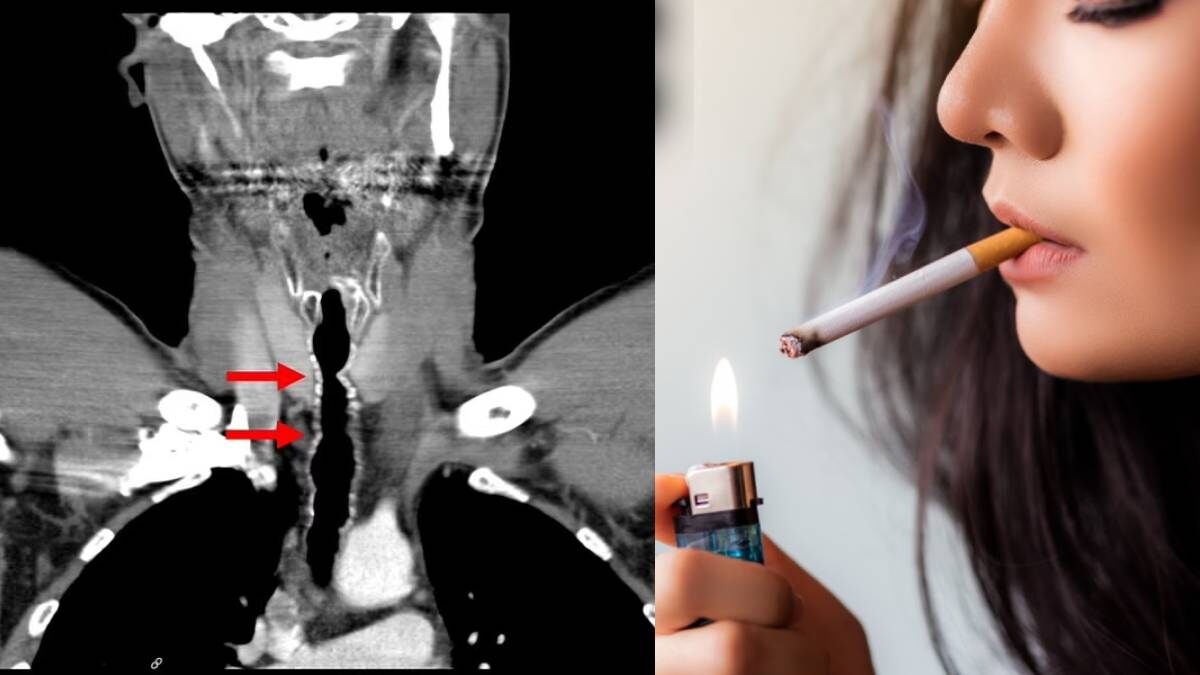

సిగరెట్ తాగడం వల్ల గొంతులో విపరీతంగా పెరిగిన వెంట్రుకలు..! అతని గతం తెలిస్తే షాక్ కావాల్సిందే..!

30 ఏళ్ల వరకు రోజుకో సిగరెట్ ప్యాకెట్ తాగడం వల్ల ఒక వ్యక్తికి అరుదైన వ్యాధి సోకింది. అతని గొంతులో లోతుగా జుట్టు పెరిగింది. కొన్నేళ్ల నుంచి క్రమక్రమంగా అతని గొంతు బొంగురు పోవడం తరువాత విపరీతమైన దగ్గు రావడం ఇప్పుడు గొంతులో మొత్తం వెంట్రుకలు రావడం చూసి వైద్యులు కూడా ఆశ్చర్యపోతున్నారు.

ఆస్ట్రియాకు చెందిన ఈ సమస్యను ఎదుర్కొంటున్నాడు. 1990లో తనకు 20 ఏళ్లు వున్నప్పుడు ఈ వ్యక్తి సిగరెట్ తాగడం ప్రారంభించాడు. అప్పటి నుంచి రోజుకు కనీసం ఒక ప్యాకెట్ సిగరెట్ కాల్చాడంటే పరిస్థితి ఎలా వుందో అర్థం చేసుకోవచ్చు. 2007లో గొంతు బొంగురు పోయి దగ్గడం వల్ల నోటిలోంచి వెంట్రుకలు బయటపడ్డాలి. ఇదేంటని వైద్యుల వద్దకు తీసుకెళ్తే కెమెరాను గొంతు లోపలికి పంపించారు. గొంతుకు ఆపరేషన్ చేయడం వల్ల అతని గొంతులో ఒక చోటు నుంచి వెంట్రుకలు విపరీతంగా పెరుగుతున్నట్లు కనుగ్గొన్నారు.

వెంట్రుకలను ఎన్ని సార్లు తొలగించినా అవి మళ్లీ మళ్లీ పెరుగుతూనే వున్నాయ్. 14 సంవత్సరాలు ఇలా చికిత్స చేసుకోవడం మళ్లీ వెంట్రుకలు రావడం నిరంతరంగా జరగింది. ఇక వైద్యులు 2022లో అతని గొంతులో ఎక్కడి నుంచైతే వెంట్రుకలు విపరీతంగా పెరుగుతూ వున్నాయో ఆ గొంతుకు సంబంధించిన కణాలను కాల్చి వేశారు.

అయితే గొంతులో ఇలా కావడానికి కారణం ధూమపానం ఎక్కువగా కాల్చడమేనని వైద్యులు తేల్చారు. అతనికి పెట్టుకతోనే గొంతులో 2 ఇంచుల సైజులో 9 వెంట్రుకలు వుండేవి. సిగరెట్ తాగడం వల్ల ఆ వెంట్రుకలు మరింత పెరిగాయ్.

ఈ రోగి ఫ్లాష్ బ్యాక్కు వెళ్తే మరో కొత్త కథ మిమ్మల్ని ఆశ్చరపరుస్తుంది. రోగి 10 ఏళ్లు వున్నప్పుడు నీళ్లల్లో మునిగిపోయాడు. గంతు కింద వుండే భాగం కొంత కట్ అవడం వల్ల అక్కడ శస్త్ర చికిత్స జరిగింది. ఈ శస్త్ర చికిత్సలో రోగికి సంబంధించిన చెవి నుంచి చర్మాన్ని తీసి గొంతుకు పెట్టారు.

పదేళ్లప్పుడు ఆపరేషన్ జరిగితే 16 ఏళ్ల వయసు నుంచి సిగరెట్ తాగడం ప్రారంభించాడు. అప్పటి నుంచి రాత్రుళ్లు సరిగ్గా ఊపిరి కూడా తీసుకోవడం రావడం లేదని తన అనుభవాలను చెప్పాడు. అప్పటి నుంచి 15 ఏళ్ల వరకు ఎన్ని చికిత్సలు చేసినా వెంట్రుకలు పెరుగుతూనే వున్నాయ్. 16 ఏళ్లప్పటి నుంచి ప్రారంభమైన సమస్య అతనికి 49 ఏళ్ల వయసులో తీరింది. ఇప్పుడు 2022లో శస్త్ర చికిత్స చేసి గొంతులు ఎక్కడి నుంచైతే వెంట్రకలు పెరుగుతున్నాయో అక్కడ గొంతులోని భాగాన్ని కాల్చి వేశారు. ఇక అక్కడి నుంచి వెంట్రుకలు పెరగకుండా ఆగిపోయాయ్.